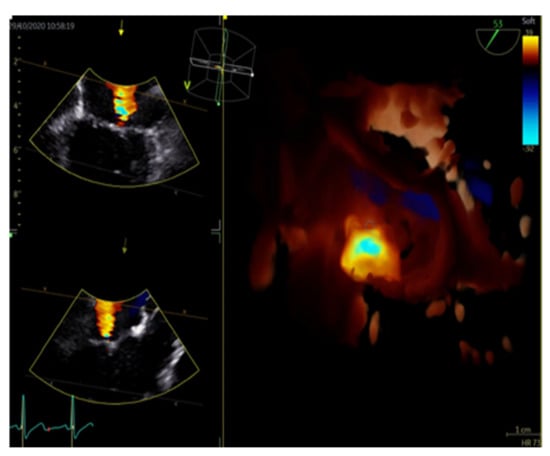

Figure 5. Three-dimensional image of the mitral valve along with color Doppler to visualize mitral regurgitation flow.

3.3. Three-Dimensional Echocardiography (3DE)

Three-dimensional echocardiography (3DE) is a relatively new innovative technique, which has become an extremely valuable asset in cardiac imaging. The miniaturization of electronics and the advancement of in-element interconnection technology has resulted in the development of matrix array transducers, which allow the acquisition of large pyramidal data sets. After highly sophisticated signal analysis combined with increased computational processing power, we can produce realistic real-time three-dimensional representations of the heart structures with a high temporal and spatial resolution (Figure 4 and Figure 5). From these 3D models we can extract useful information concerning the volume quantification of cardiac chambers, realistic anatomical views of valves, as well as precise oversight of regurgitant lesions and shunts. Indeed, 3DE color Doppler imaging offers a new perspective in the evaluation of cardiac function. Last but not least, with the revolutionary advancement of percutaneous structural procedures such as transfemoral aortic valve replacement, clip therapy for mitral and tricuspid valve pathology, occlusion devices, etc., real-time 3DE echocardiography has become indispensable for the accurate guiding and monitoring of these procedures in the catheterization laboratory [5,6,7].